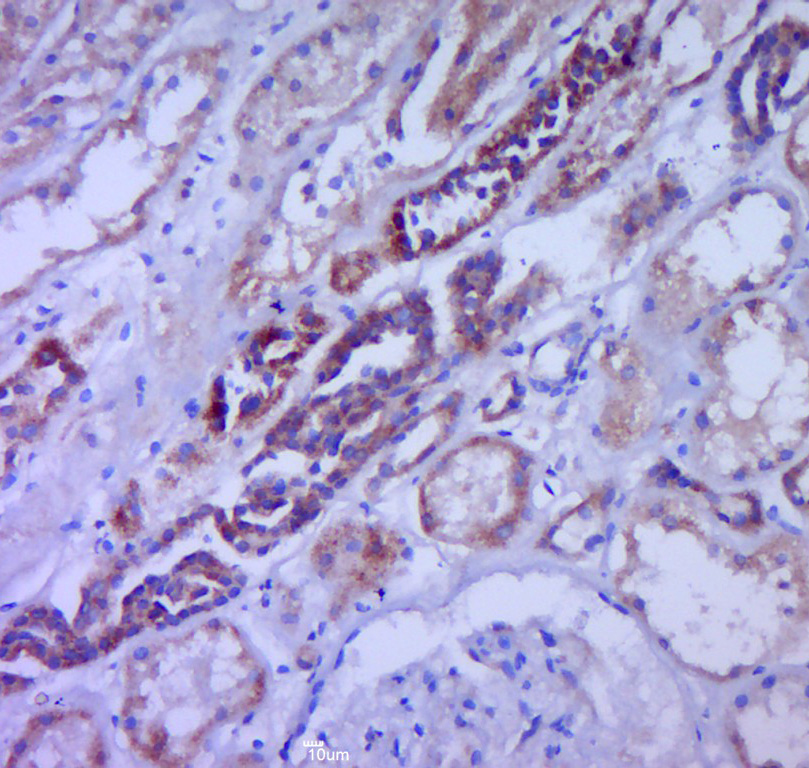

Paraformaldehyde-fixed, paraffin embedded (Mouse brain); Antigen retrieval by boiling in sodium citrate buffer (pH6.0) for 15min; Block endogenous peroxidase by 3% hydrogen peroxide for 20 minutes; Blocking buffer (normal goat serum) at 37°C for 30min; Antibody incubation with (G-CSF) Polyclonal Antibody, Unconjugated (bs-1023R) at 1:400 overnight at 4°C, followed by operating according to SP Kit(Rabbit) (sp-0023) instructionsand DAB staining.

Paraformaldehyde-fixed, paraffin embedded (human kidney tissue); Antigen retrieval by boiling in sodium citrate buffer (pH6.0) for 15min; Block endogenous peroxidase by 3% hydrogen peroxide for 20 minutes; Blocking buffer (normal goat serum) at 37°C for 30min; Antibody incubation with (CSF3) Polyclonal Antibody, Unconjugated (bs-1023R) at 1:400 overnight at 4°C, followed by a conjugated secondary (sp-0023) for 20 minutes and DAB staining.

Paraformaldehyde-fixed, paraffin embedded (human brain glioma); Antigen retrieval by boiling in sodium citrate buffer (pH6.0) for 15min; Block endogenous peroxidase by 3% hydrogen peroxide for 20 minutes; Blocking buffer (normal goat serum) at 37°C for 30min; Antibody incubation with (CSF3) Polyclonal Antibody, Unconjugated (bs-1023R) at 1:400 overnight at 4°C, followed by a conjugated secondary (sp-0023) for 20 minutes and DAB staining.